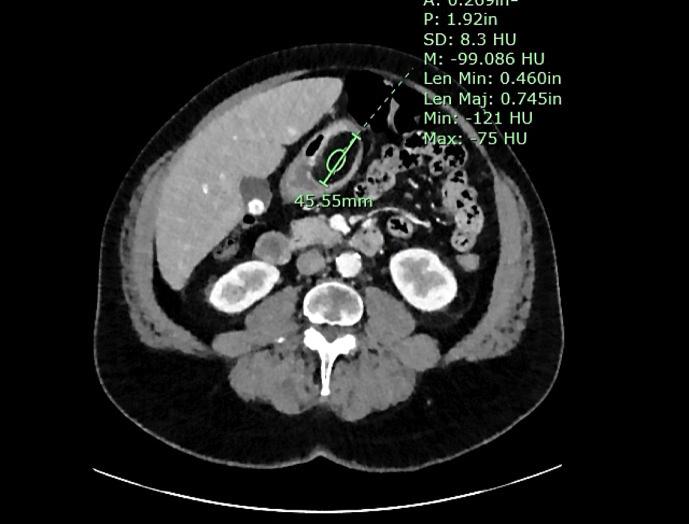

The purpose of this case series was to review a rare subset of tumors known as gastric lipomas, which are typically found incidentally. The motivation for this study arose from the identification of 2 cases within our institution in a short period.

CASE PRESENTATION

The study involved a review of the diagnosis and management of 2 patients presenting with gastric lipomas at our institution after symptoms of gastrointestinal bleeding. With the advent of new radiologic investigations such as computed tomography and magnetic resonance imaging and advances in endoscopy, there are new approaches to identifying and managing these tumors. On further evaluation of the literature, we found that despite the availability of minimally invasive endoscopic techniques such as mucosal resection and submucosal dissection in the setting of large tumors, most patients tend to have to resort to surgical management.

本病例系列的目的是回顾一类罕见的肿瘤,即胃脂肪瘤,这类肿瘤通常是偶然发现的。本研究的动机源于我们机构在短时间内确诊的2例病例。

病例介绍

本研究回顾了我院2例出现胃肠道出血症状后被诊断为胃脂肪瘤的患者的诊断和治疗情况。随着计算机断层扫描和磁共振成像等新的放射学检查方法的出现以及内镜技术的进步,出现了识别和处理这些肿瘤的新方法。在进一步查阅文献时,我们发现,尽管对于较大的肿瘤可以采用黏膜切除和黏膜下剥离等微创内镜技术,但大多数患者往往仍需采取手术治疗。